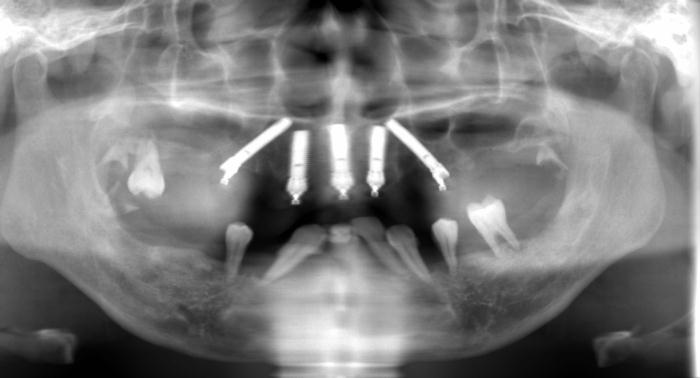

当院ではCTを院内に設置しておりますので、大学病院などに撮影に行くことはありません。

CTは、レントゲンではわからない骨や神経の位置や状態を把握することが可能で、安全なインプラント手術を行うことが可能です。

インプラント治療は、歯が抜けてしまった部分に人工歯根を埋入し人工歯をかぶせる治療法です。

インプラント本体は手術によって顎骨に埋め込みますが、顎の骨としっかりと結合・固定されるため、健康な自分の歯のようにしっかりと噛むことができるように機能性が回復します。